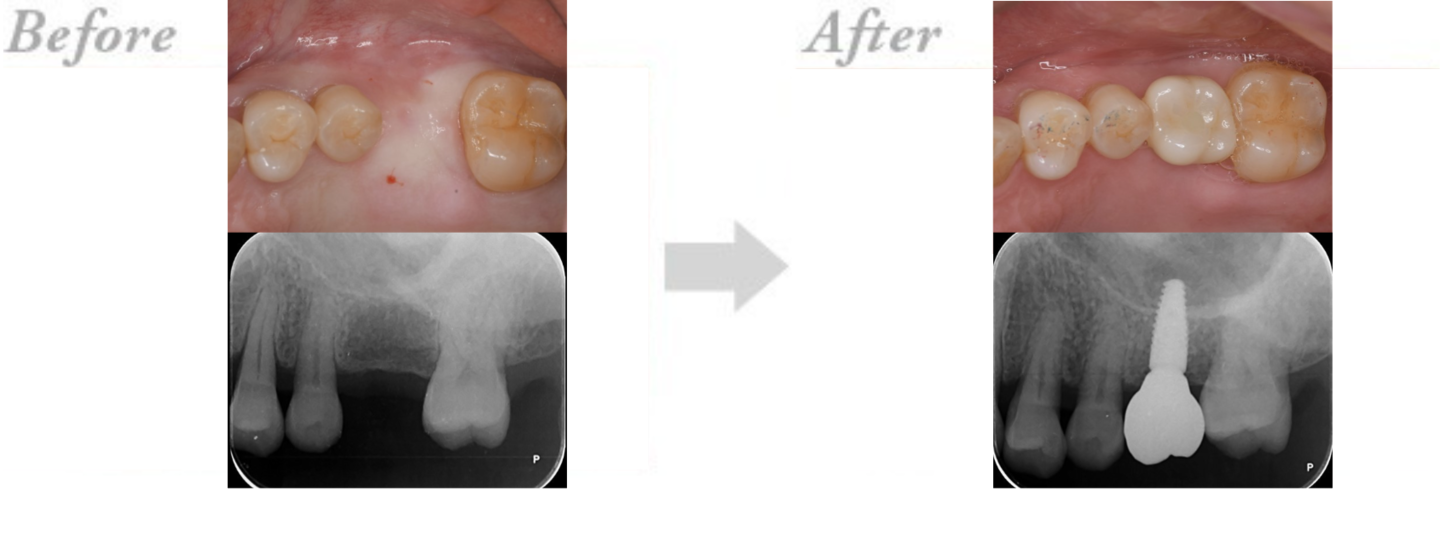

◆インプラント治療の実例 CASE2